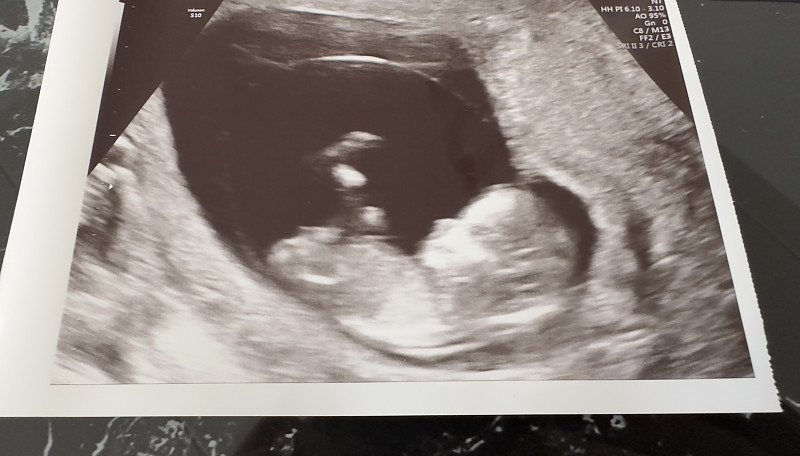

- Nėštumas